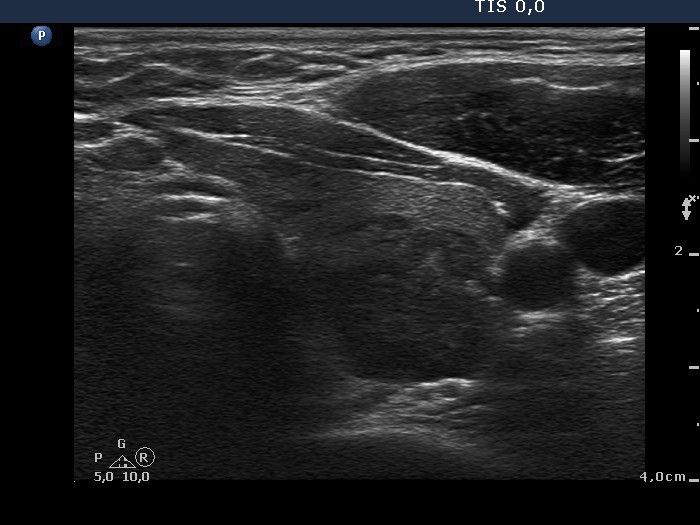

Chronic lymphocytic thyroiditis - Case 45. |

Clinical presentation: a 54-year-old patient was referred for an evaluation of a 'nodular goiter' detected on a sonographic screening.

Functional state: subclinical hypothyroidism (TSH 5.18 mIU/L, FT4 12.4 pM/L).

Ultrasonography: the thyroids contained multiple hypoechogenic areas. These do not fit a nodule because of their shape. See longitudinal sections and video.

Comment: it is worth to analyze the video and the longitudinal section of the left lobe. In contrast with a true nodule, these hypoechogenic areas are irregular in shape.